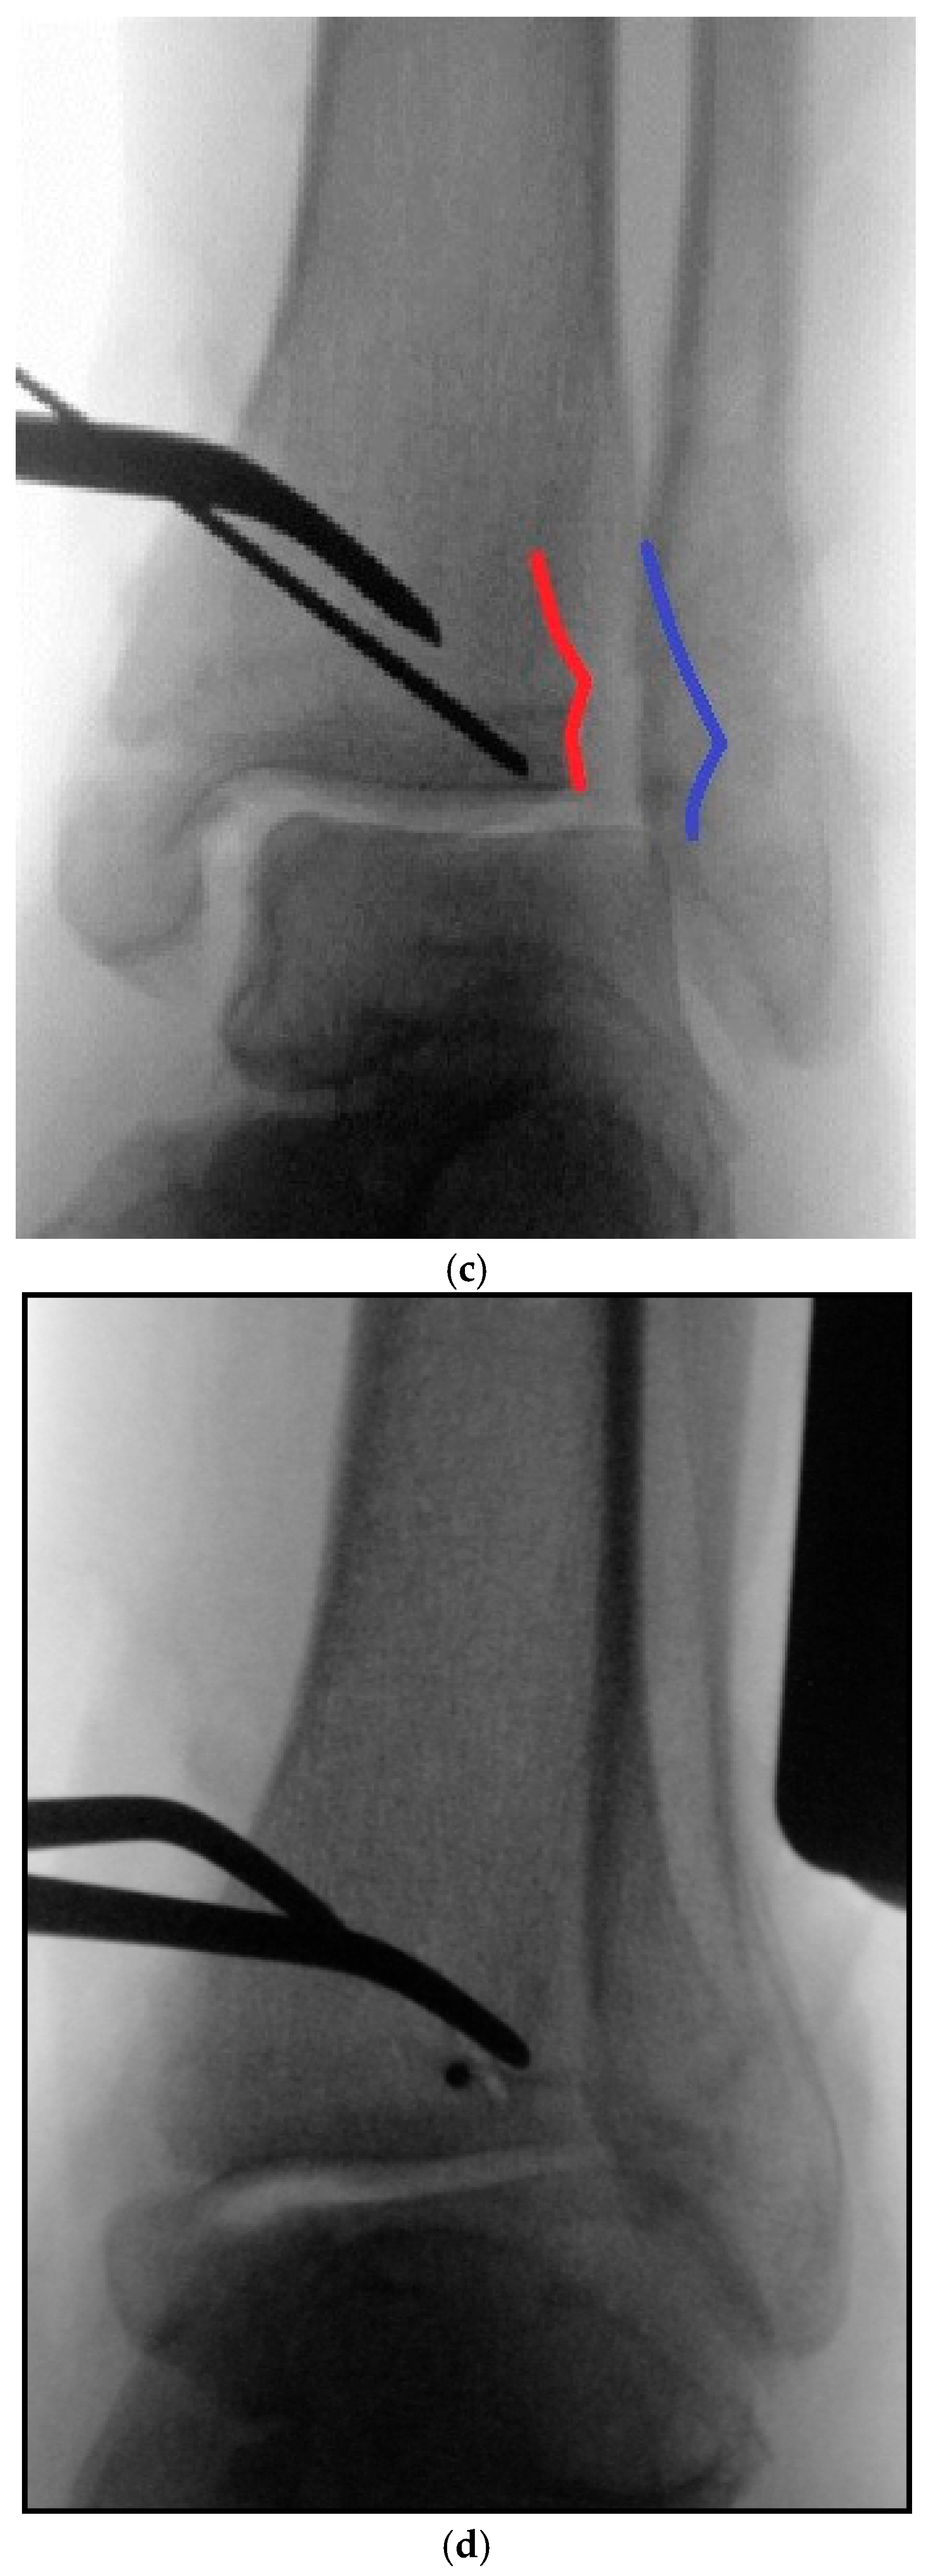

5.2. Inside-Out Fixation of the Posterior Malleolus Using a Headless Double-Threaded Compression Screw

5.4. Medial Malleolar Cancellous Screw Fixation Using the Modified Posteromedial Approach